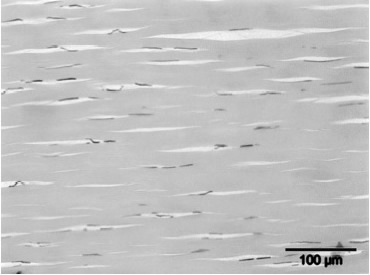

2) Radiaal

Schokgolven geproduceerd door een pneumatische hamer worden radiaal uitgezonden. Dit betekent dat de intensiteit van de schok het hoogste is aan het oppervlak (de huid) en verder weg van de hamer, steeds lager wordt. De schokgolven divergeren. Dit type van ESWT is geschikt voor de behandeling van oppervlakkige structuren. De behandeling van diepe structuren is moeilijker omdat de schokgolven veel energie verliezen alvorens ze arriveren op “the place to be". Door sommigen wordt in vraag gesteld of dit type toestel echt beschouwt kan worden als een ESWT-toestel, dan wel als pneumatisch hamer.